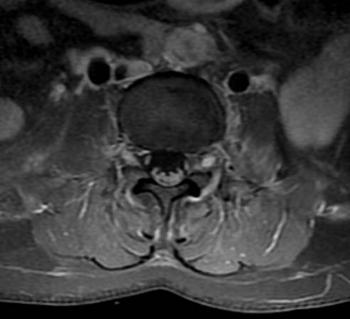

Another study analyzed the imaging results of three target groups affected by Zika: adults who developed acute neurological syndrome, newborns with vertical infection with neurological disorders, and pregnant women with rash outbreaks suggestive of Zika.

Many of the adults had symptoms of Guillain-Barré syndrome, a rare disorder in which the body's immune system attacks the nervous system causing rapid onset muscle weakness. A few showed inflammation of the brain and spinal cord (Bickerstaff's encephalitis) or brain stem and spinal cord lesions. Common MRI findings included enhancement of certain spinal and facial nerves. In the newborns, MRI showed orbital injuries and anatomical changes in brain tissue.

"It was alarming to find so many cases of neurological syndromes in adults, some very serious, related to Zika virus infection," said study author Emerson de Melo Casagrande, M.D., from the Department of Radiology at Antonio Pedro University Hospital - Federal Fluminense University. "We have also noticed a difference between these syndromes, even though the trigger was the same."